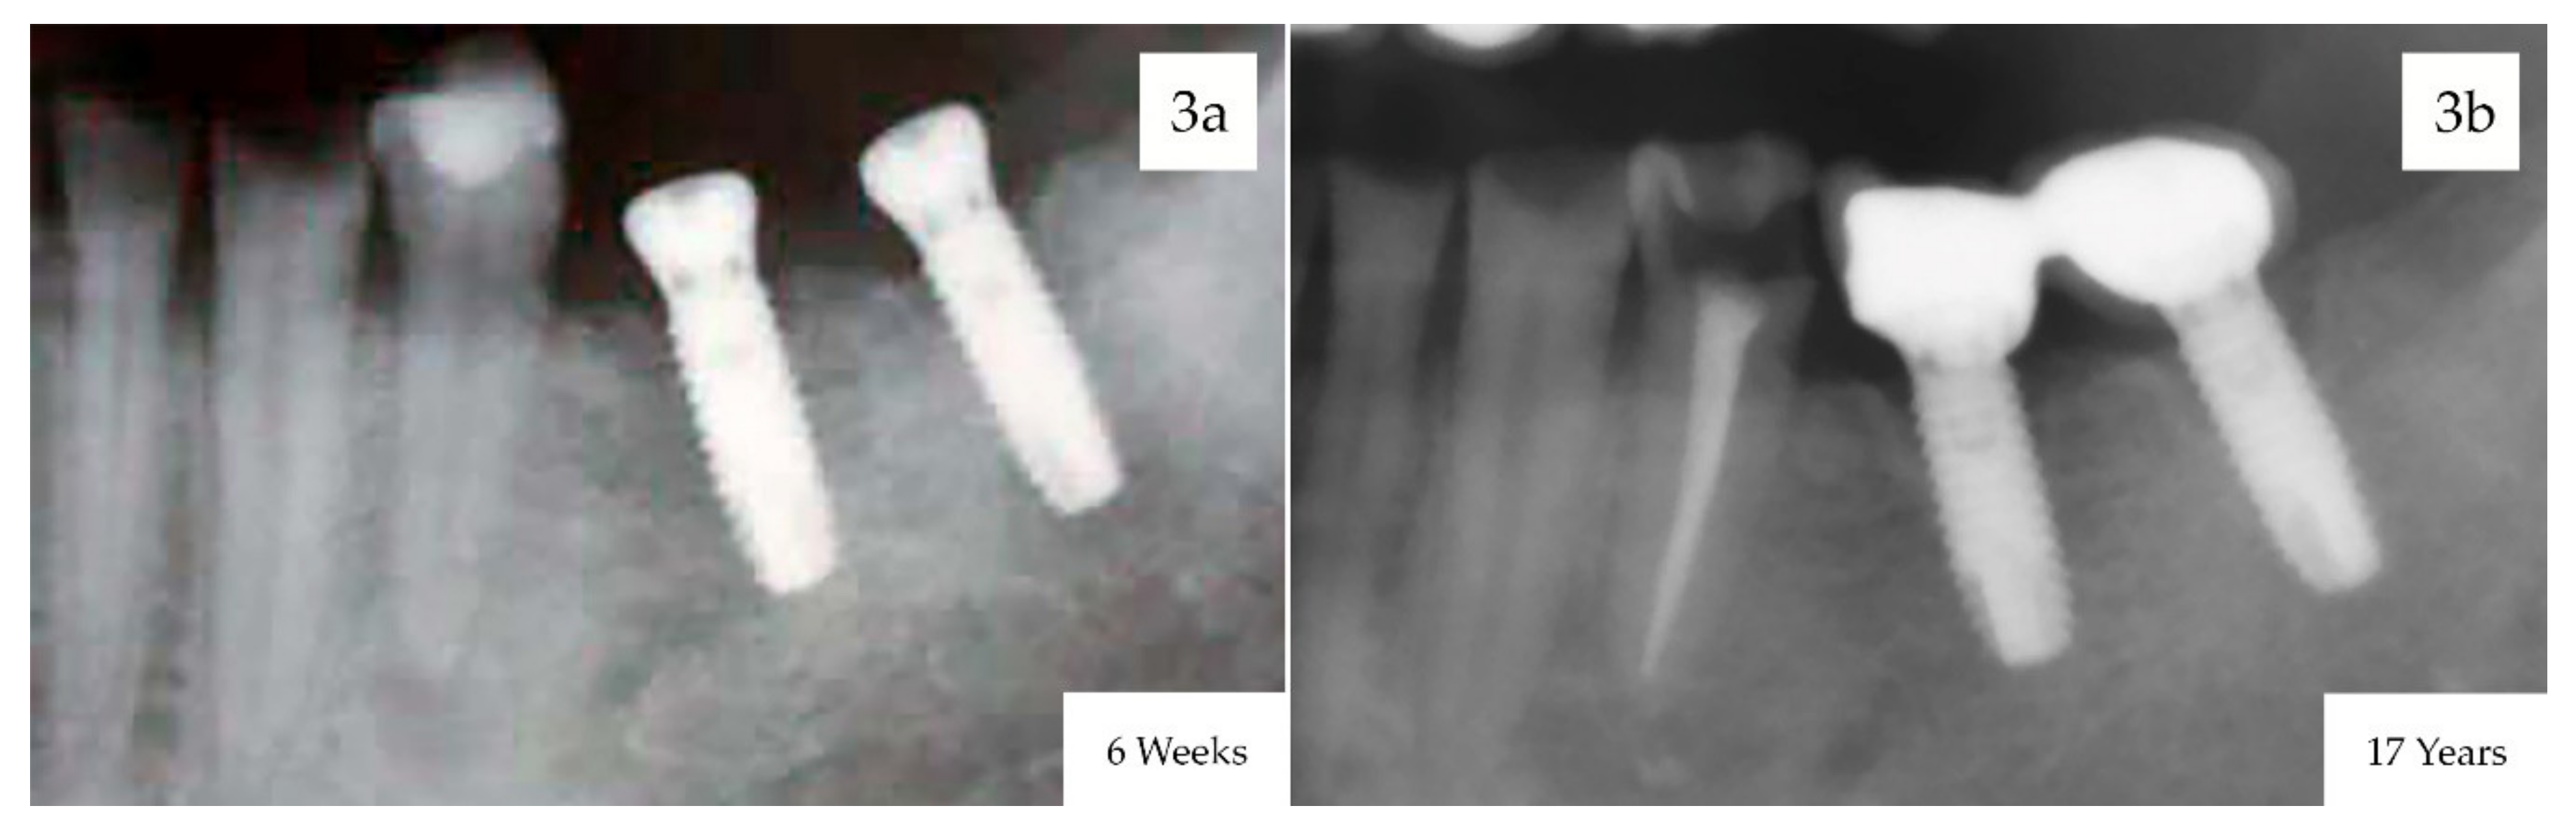

3. Results